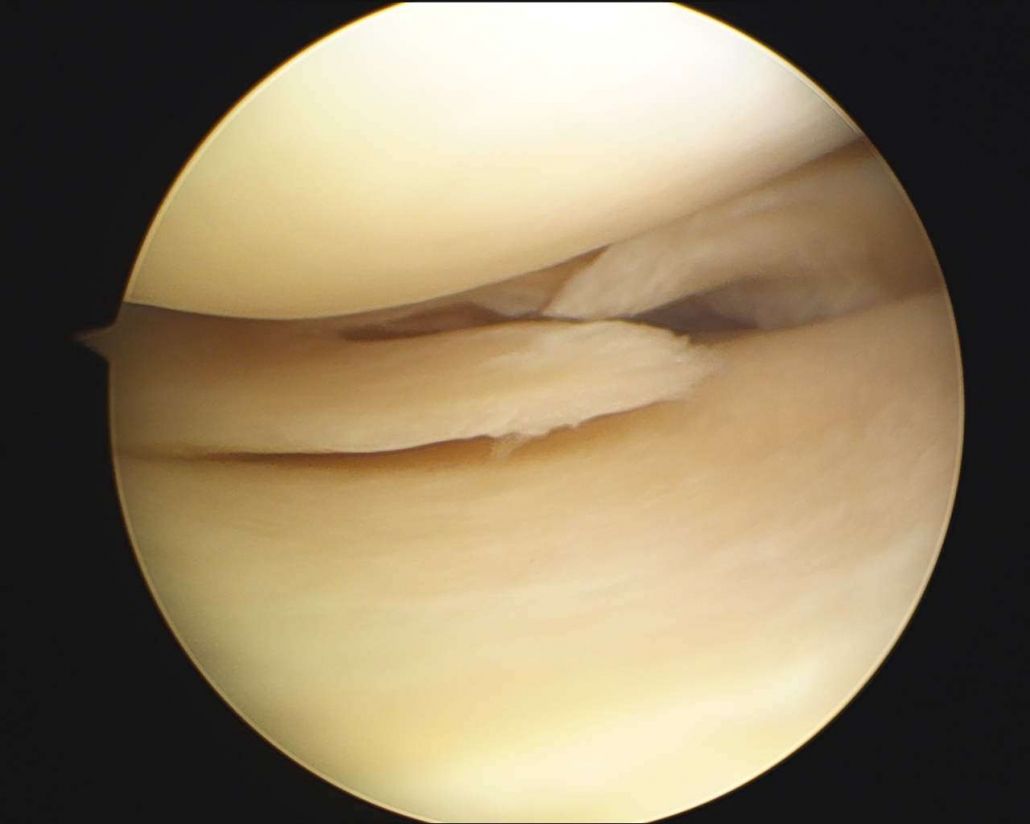

MENISCO ROTO:

Imagen: se aprecia una ruptura del menisco visto con artroscopia.